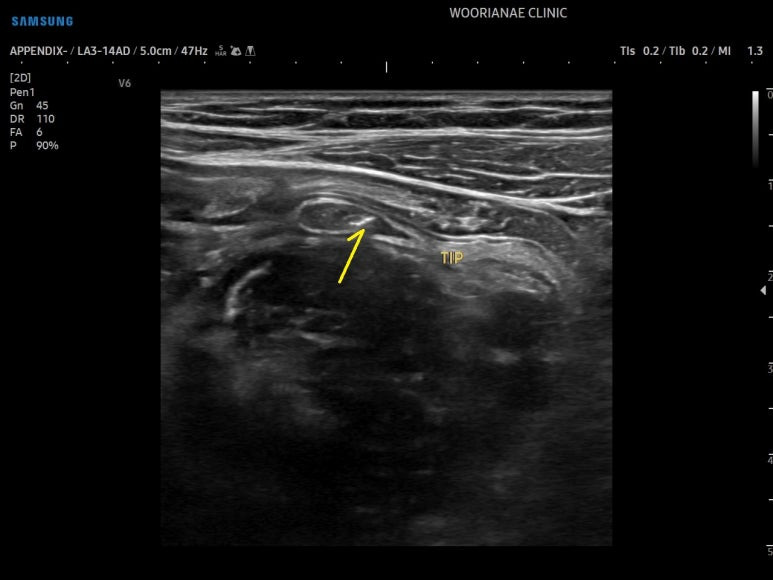

충수의 끝까지 확인, 정상 소견

충수내에 대변돌, appendicolith, fecalith의 관찰 (화살표)